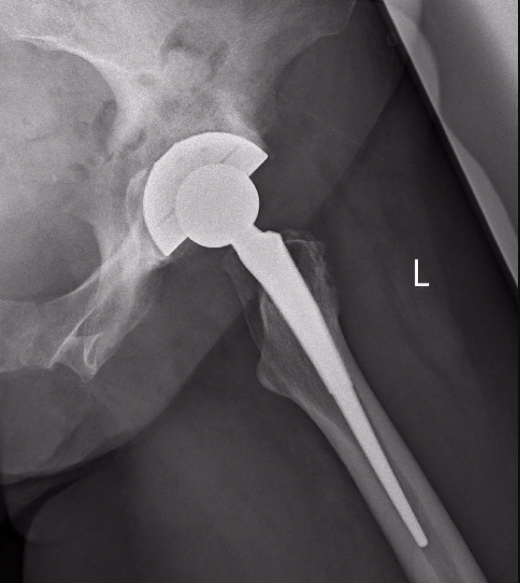

Because each patient’s body is different, each patient needs their replacement joints to be sized and positioned differently. However, current surgery planning relies on 2D X-rays and manual manipulation by surgeons, with existing planning software not accounting for the biomechanics of the joint.

Formus’s software is the world’s first automated 3D planner for joint replacement surgeries. It combines medical imaging data with biomechanical simulation to create a 3D model of a patient’s joint, then selects and places implants that restore the native biomechanics. Surgeons can interact with the 3D model to adjust the plan according to their expertise and preferences. It also speeds up surgery planning from weeks to hours.